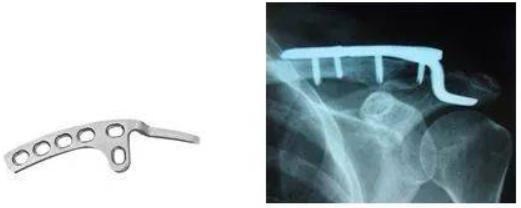

②钢板影响外观、心理或潜在影响关节活动

有些钢板如踝关节下端钢板,虽在皮下,但一般板不会引起患者不适。但有些钢板影响患者的外观、心理和关节活动,如锁骨骨折钩钢板、掌指骨骨折、肘关节骨折、髌骨骨折、踝关节骨折钢板等,长期放在体内会潜在影响关节活动,因此即使无不适症状也建议取出。